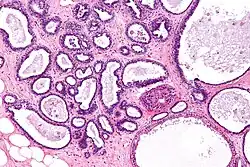

Cystic hyperplasia of endometrium | Micrograph showing cystic hyperplasia of endometrium. Cystically dialated glands are lined by proliferative type of epithelium. Stroma also resembles proliferative phase. No atypia is seen in the cells. | Category: Histopathology of hyperplasia endometrium | Cystic hyperplasia |

![]() |